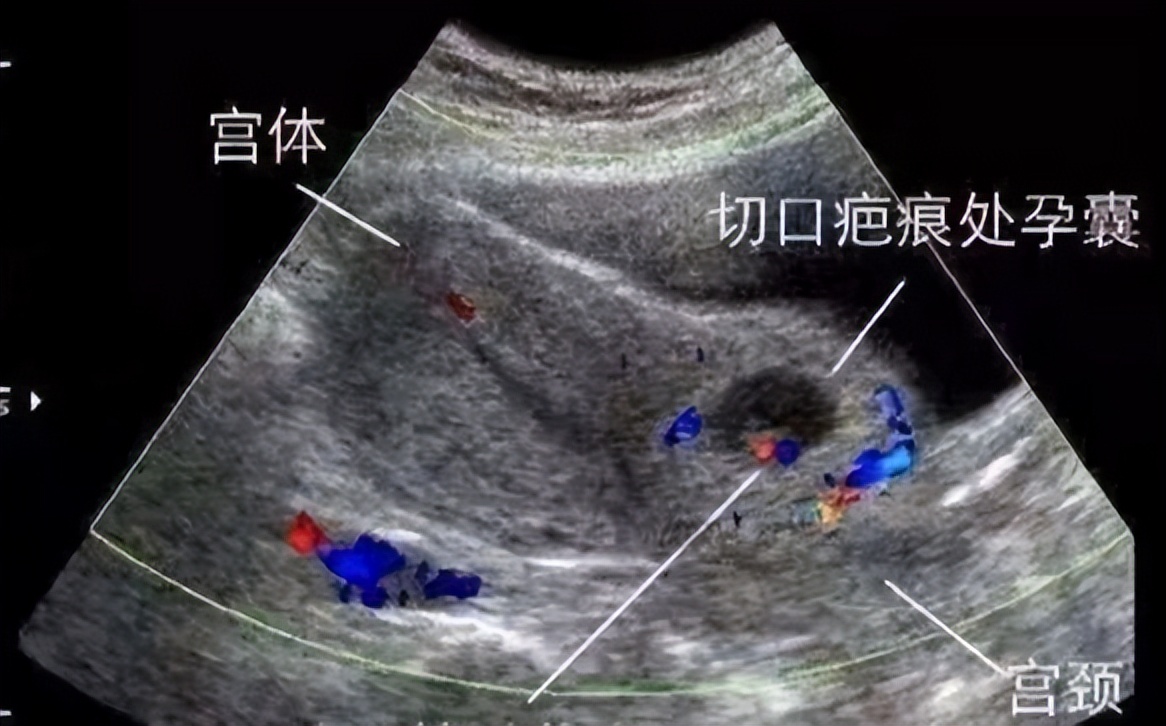

这是2023年6月6日发生在陕西中医药大学第二附属医院秦都院区产五科的一幕。患者是一位双子宫且有过两次剖宫产史的孕妇,瘢痕妊娠50余天,给予药物杀胚治疗3天,无明显效果,在县医院清宫术开始刚2分钟,阴道出血如泉涌,10分钟就有400ml鲜红色血液涌出。患者随即出现头晕、乏力的状况。在当地医院给予备血、填塞、止血等治疗均效果不佳,出血不止,累计出血量达到了800ml。情况危急,该院立刻向秦都院区产五科主任车虹彩打电话急救。车虹彩立即向值班医师张红英副主任医师通知,做好产后出血II级预案并立即组织抢救。

晚上7时左右,救护车抵达陕西中医药大学第二附属医院。接到患者,医生紧张情绪立马涌上心头,患者精神状态差,面色苍白,痛苦病容,急性失血貌,下腹部胀痛难忍,阴道仍有活动性出血,经过快速诊断,患者为产后出血、失血性贫血、瘢痕妊娠。张红英迅速指挥医护人员兵分三路,一路立即将患者送入介入室,准备行子宫动脉造影+灌注+栓塞术;一路抽血完善检查并积极配血,负责给予止血等急救药物,监护生命体征;一路协助家属办理住院手续。7点35分,介入手术开始。介入造影显示双侧子宫动脉增粗、迂曲,子宫中下段可见斑片状异常染色,术中情况与料想的一样,立即给予双侧子宫动脉灌注稀释甲氨蝶呤注射液100mg,再使用明胶海绵栓塞颗粒栓塞子宫动脉,未见异常染色,经过半小时的手术,出血停止了,患者面色渐转红润,生命体征平稳,紧张的气氛终于缓和。

近年来,由于剖宫产率居高不下,瘢痕妊娠的发生率也呈上升趋势,由于子宫峡部肌层较薄弱,加之剖宫产切口瘢痕缺乏收缩能力,瘢痕妊娠在流产或刮宫时断裂的血管不能自然关闭,可发生致命的大量出血。因此,瘢痕妊娠的女性朋友千万不能掉以轻心。陕西中医药大学第二附属医院作为陕西省及咸阳市的危重症孕产妇和新生儿救治与转诊中心,在产五科车虹彩主任的带领下,经过数年来的努力工作,积累了丰富的经验,拥有过硬的专业技术,秉承耐心、细致、热情的服务理念,为孕产妇的身心健康保驾护航。